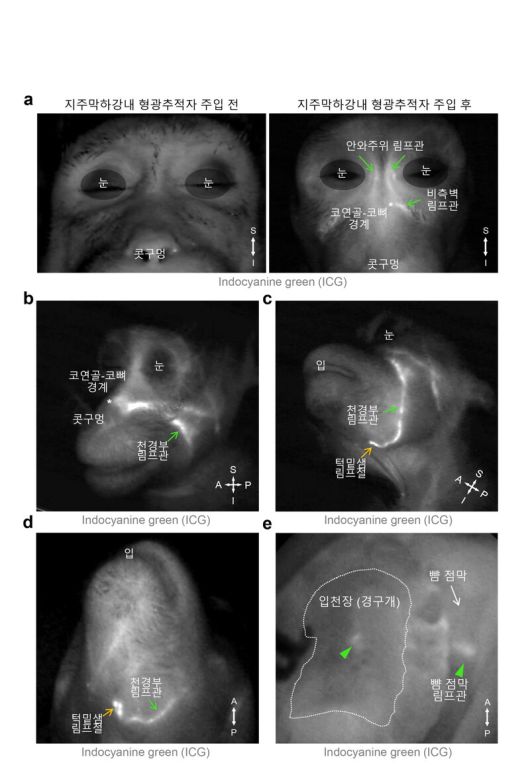

연구진은 이번 생쥐 실험에서 피부에 좀 더 가까운 배출 경로를 새롭게 알아냈다. 뇌척수액에 형광 염료를 넣어 살펴본 결과, 뇌척수액이 눈 주위와 코 안쪽, 입천장 림프관을 통해 눈, 코 옆쪽 얼굴 피부 아래의 림프관으로 모인 뒤 턱밑샘 림프절로 배출되는 걸 확인했다.

영장류에서 관찰된 뇌척수액 배출 림프관 분포. 지주막하강은 뇌와 척수를 둘러싸고 보호하는 세 개의 뇌막 중 두번째와 세번째 막 사이에 있는 공간을 말한다. 기초과학연구원 제공 |

진호경 선임연구원은 “한국생명공학연구원 국가영장류센터를 통해 이 경로가 생쥐뿐 아니라 영장류에도 존재한다는 걸 확인했다”고 말했다. 이는 사람에게도 비슷한 뇌척수액 배출 경로가 있을 가능성이 크다는 걸 시사한다.